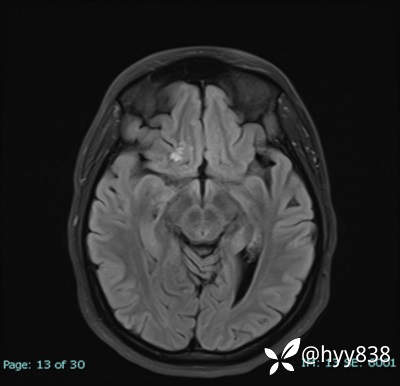

MRI sag T1WI + axi T2WI+FLAIR